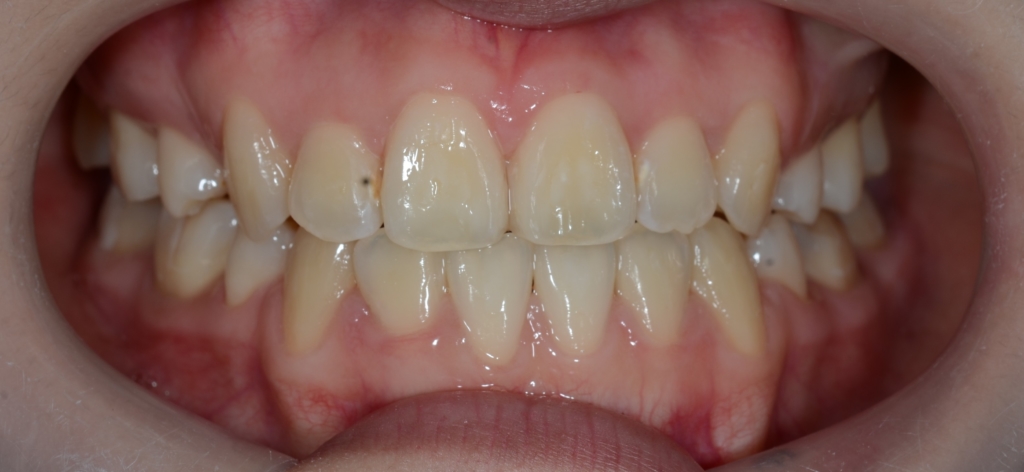

【Before】

#1.顎と歯の不調和による叢生

(前歯部の反対咬合を伴う)

#2.骨格的に下顎前突(受け口)傾向

と診断しました。